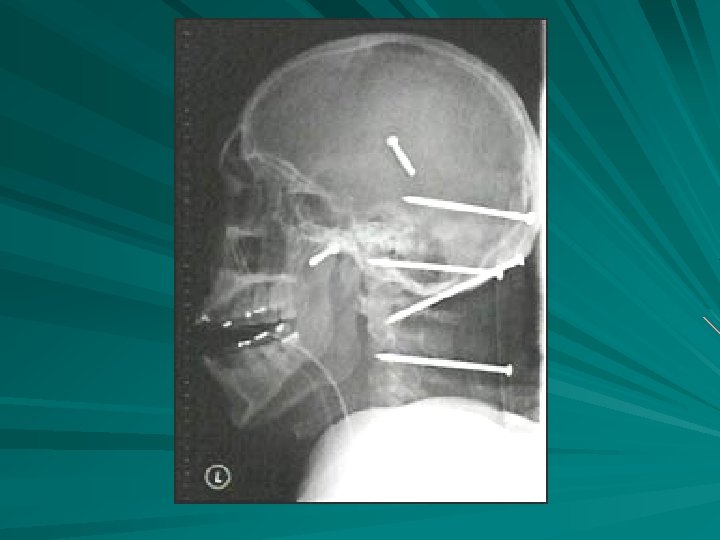

GSW TO ABD

QSW MARKING ENTRANCE /EXIT WOUNDS